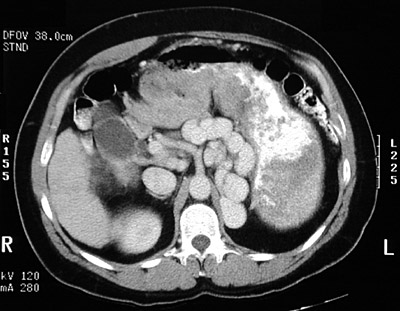

This abdominal CT scan demonstrates tortuous, enlarged veins representing gastric varices in a patient with cirrhosis of the liver. The stomach is filled with some bright contrast. The liver is small and most of it is located superiorly to this slice. Varices result from portal hypertension and increased collateral venous flow. |